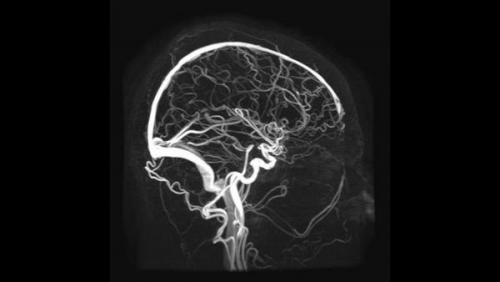

МР-ангиография сосудов головного мозга, для чего применяется?

Метод анализа сосудов головного мозга позволяет выявить сужения, расширения артерий, аневризмы, опухоли и аномалии в строении сосудов. Эта диагностика важна для предотвращения инсульта и выяснения причин головной боли, головокружения и потери сознания. Исследование назначается при подозрении на ангиому, другие опухоли, после черепно-мозговой травмы или образовании гематомы. Контрастное вещество вводится через плечевую, локтевую, надключичную или правую бедренную артерии с установкой катетера, который продвигается до нужного разветвления. Затем выполняется съемка на магнитно-резонансном томографе.